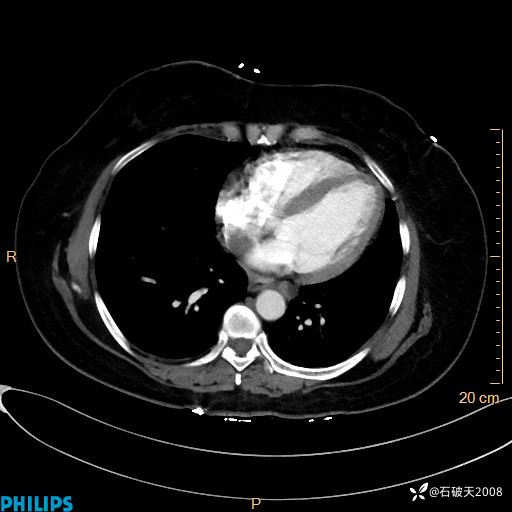

静脉期